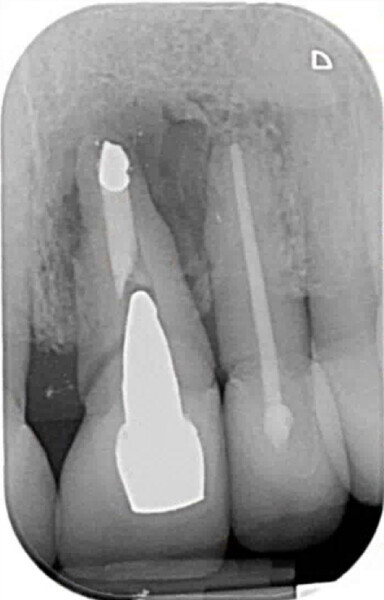

Fig. 8: Postoperative radiograph of implant placement.